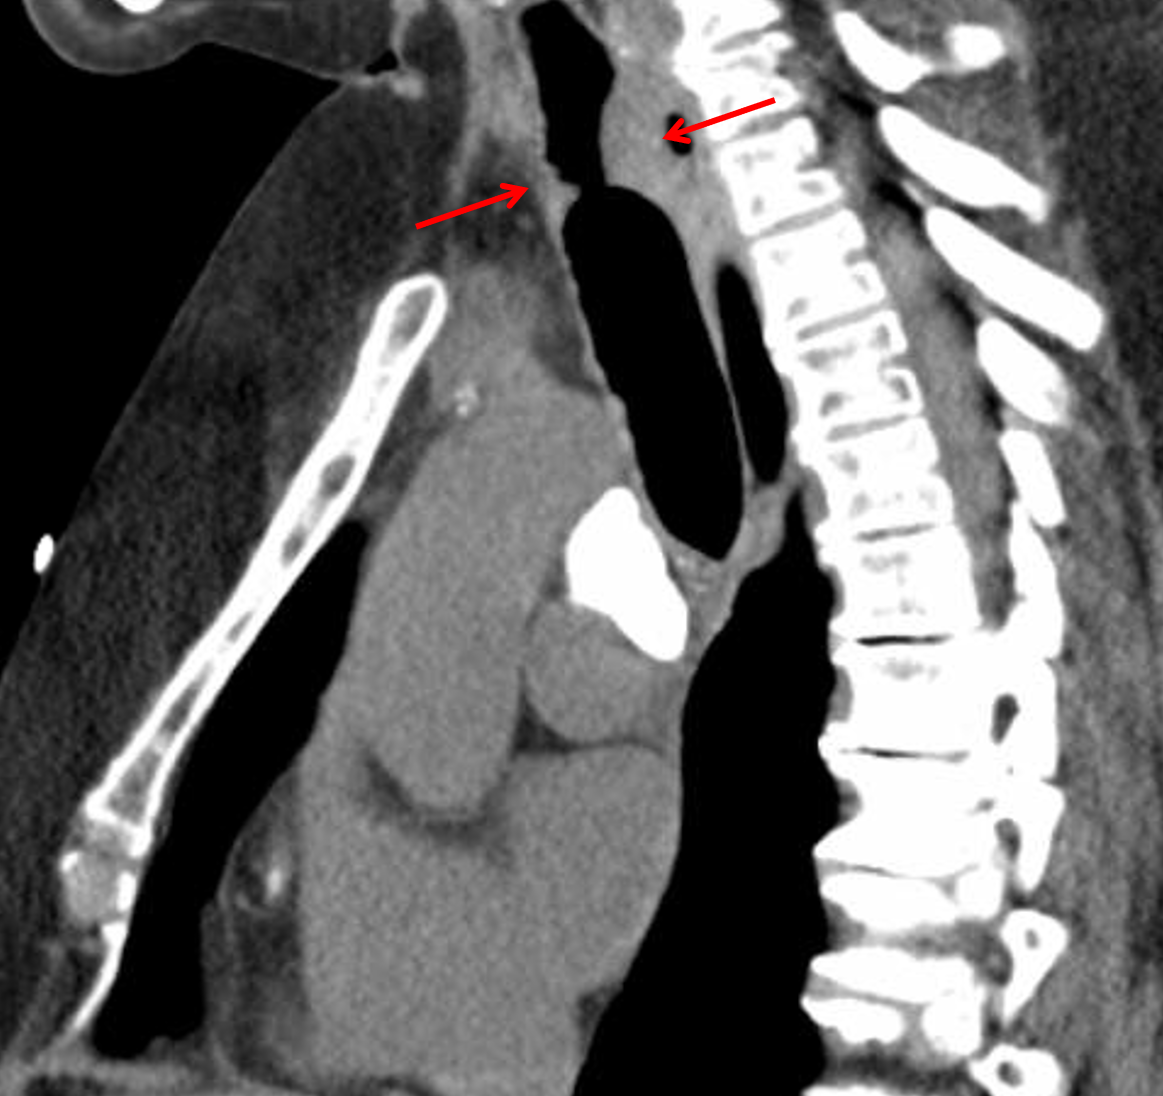

Age: 60

Sex: Female

Indication: Stridor, recent surgery

Sample ReportShort segment subglottic tracheal narrowing, which may relate to recent intubation, though neoplasm is not excluded. Consider laryngoscopy for further evaluation.

Sequela of granulomatous disease.